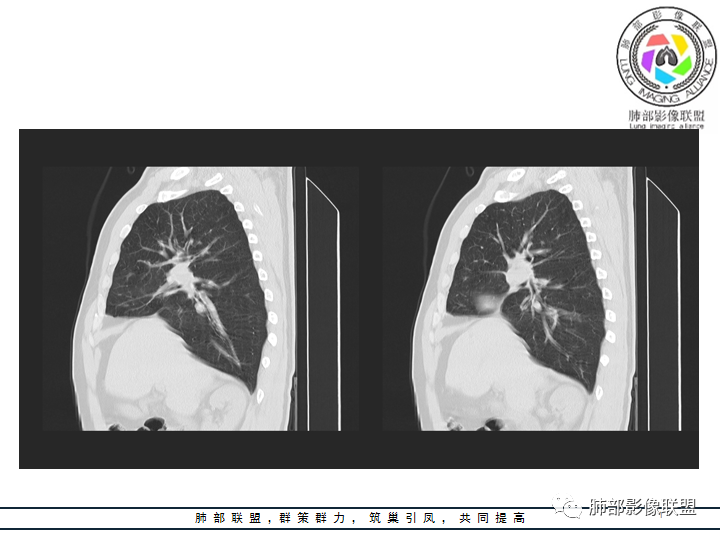

影像资料

老年男性患者,长期吸烟史,没有呼吸系统临床表现。胸部CT示右肺上叶实性密度结节影,密度均匀,未见空洞及钙化,边缘较光整,未见分叶及毛刺。血管影旁现侧出,支气管进入并截断,不均匀强化。

恶性病灶需要排除的有神经内分泌癌(大细胞癌、小细胞癌、类癌)、鳞癌、淋巴瘤样上皮癌、淋巴瘤等等。

——本例鳞癌病理意见可以符合,只是太光整、太干净,且病灶不大,未能显示出坏死等特征,我们从影像上难以得出倾向性意见。